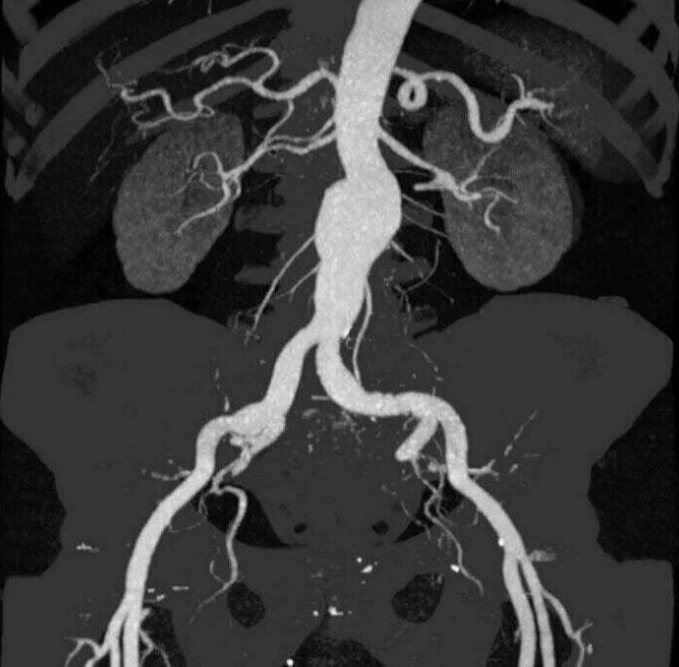

ΔΙΑΓΝΩΣΤΙΚΕΣ ΕΞΕΤΑΣΕΙΣ Κοιλιακής Αορτής και σπλαχνικών αρτηριών

Οι διαγνωστικές εξετάσεις για την αξιολόγηση της κοιλιακής αορτής και των σπλαχνικών αρτηριών μπορεί να περιλαμβάνουν τις εξής μεθόδους:

- Αγγειογραφία της Κοιλιακής Αορτής και των Σπλαχνικών Αρτηριών (Celiac Artery Angiography): Αυτή η εξέταση χρησιμοποιείται για να αξιολογήσει την κατάσταση της κοιλιακής αορτής και των αρτηριών που εξυπηρετούν τα σπλάχνα. Συνήθως, περιλαμβάνει τη χρήση χρωματιστικού υγρού για εμφανή οπτικοποίηση των αγγείων στις ακτινογραφίες.

- Σπιράλ Υπολογιστική Τομογραφία (CT Angiography - CTA): Η CTA είναι μια μέθοδος εικονογράφησης που χρησιμοποιεί την τεχνολογία της υπολογιστικής τομογραφίας για τη δημιουργία λεπτομερών εικόνων των αγγείων. Συνήθως, περιλαμβάνει και τη χρήση χρωματιστικού υγρού για καλύτερη οπτικοποίηση των αγγείων.

- Μαγνητική Αξονική Τομογραφία (Magnetic Resonance Angiography - MRA): Η MRA είναι μια μέθοδος που χρησιμοποιεί το μαγνητικό πεδίο για τη δημιουργία εικόνων των αγγείων. Συνήθως, δεν απαιτεί τη χρήση χρωματιστικού υγρού.

- Δοπλερογραφία των Σπλαχνικών Αρτηριών (Doppler Ultrasound of Splanchnic Arteries): Η δοπλερογραφία χρησιμοποιείται για τον έλεγχο της ροής του αίματος στις σπλαχνικές αρτηρίες και την ανίχνευση πιθανών προβλημάτων, όπως στενώσεις ή ανευρύσματα.

Ο ιατρός θα επιλέξει την κατάλληλη μέθοδο ανάλογα με τα συμπτώματα, την ιατρική ιστορία και τις ανάγκες του ασθενούς.